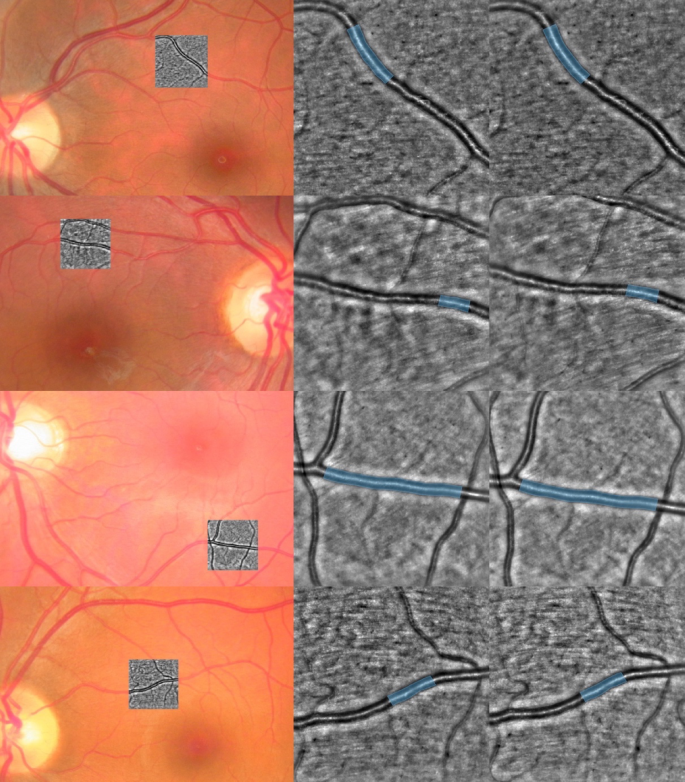

All acquired images were exported for further processing. A grader manually segmented a vessel portion using custom-made software allowing to zoom in and out, image panning, and mouse pointing at rtx1 images to define the vessel lumen. All 12 images (three images per acquisition type: Basal 1, Contra, Basal 2, and Ipsi) were individually segmented by the same grader. Image examples and respective segmentation can be seen in Fig. 3. One independent grader assessed all segmentations, and another assessed segmentation by sampling the dataset.

Two healthy control (top) and two diabetic patients (bottom) examples. From top to bottom: cases HC03, HC08, DM02 and DM04. Left: color fundus photography with the rtx1 shown overlapped in grayscale. Middle/Right: full-size rtx1 images (4 × 4 degree field-of-view, 1500 × 1500 pixels) after the contralateral/ipsilateral stimulation. Analyzed vessel segment in blue. Additional example cases can be seen in the Supplementary figures.